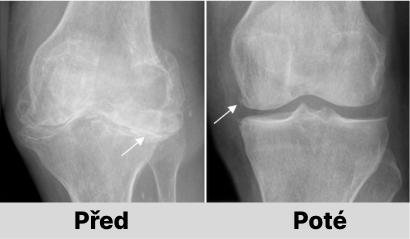

Jaroslava Melicharová: Určitě to možné je. Pokud nedošlo k nevratným patologickým změnám v kostech, lze vše napravit odstraněním příčiny pomocí AntiZynt. Náš výzkum dokazuje, že již za 1-1,5 měsíce nepřetržitého užívání AntiZynt je možné obnovit klouby i u těžkých forem osteoartrózy a artrózy.

U 99,2 % osob trpících různými revmatickými onemocněními (osteochondróza, artróza, artritida, osteoporóza, dna, dysplazie kloubů, sklerodermie atd.) došlo během 2 měsíců po užívání AntiZynt k úplnému uzdravení kloubů. Osoby se zbavily bolesti a dalších příznaků a také pohyblivost kloubů se vrátila do normálu.